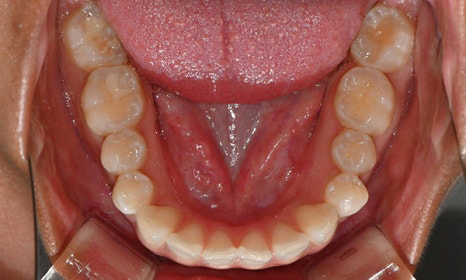

치아 상태는 어땠냐면요:

위아래 앞니 사이에 공간이 벌어져 있었어요.

앞니가 삐뚤빼뚤한 덧니도 있었죠.

윗니와 아랫니가 너무 깊게 맞물리는

과개교합이 있었어요.

왼쪽 아래 작은어금니가 90도 돌아가 있었는데,

이로 인해 왼쪽 치아 배열과 교합이 좋지 않았죠.

초진시 구내사진 (2025. 3.31)